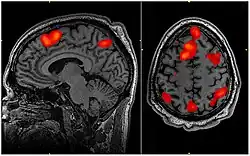

Notations: let FMRI stand for functional magnetic resonance imaging.

In the image on the right: "Working memory tasks typically show activation in the bilateral and superior frontal cortex as well as in parts of the superior bilateral parietal cortex. The highlighted regions showed significantly different activation between an individual performing a 1-Back task versus a 2-Back task."[11]